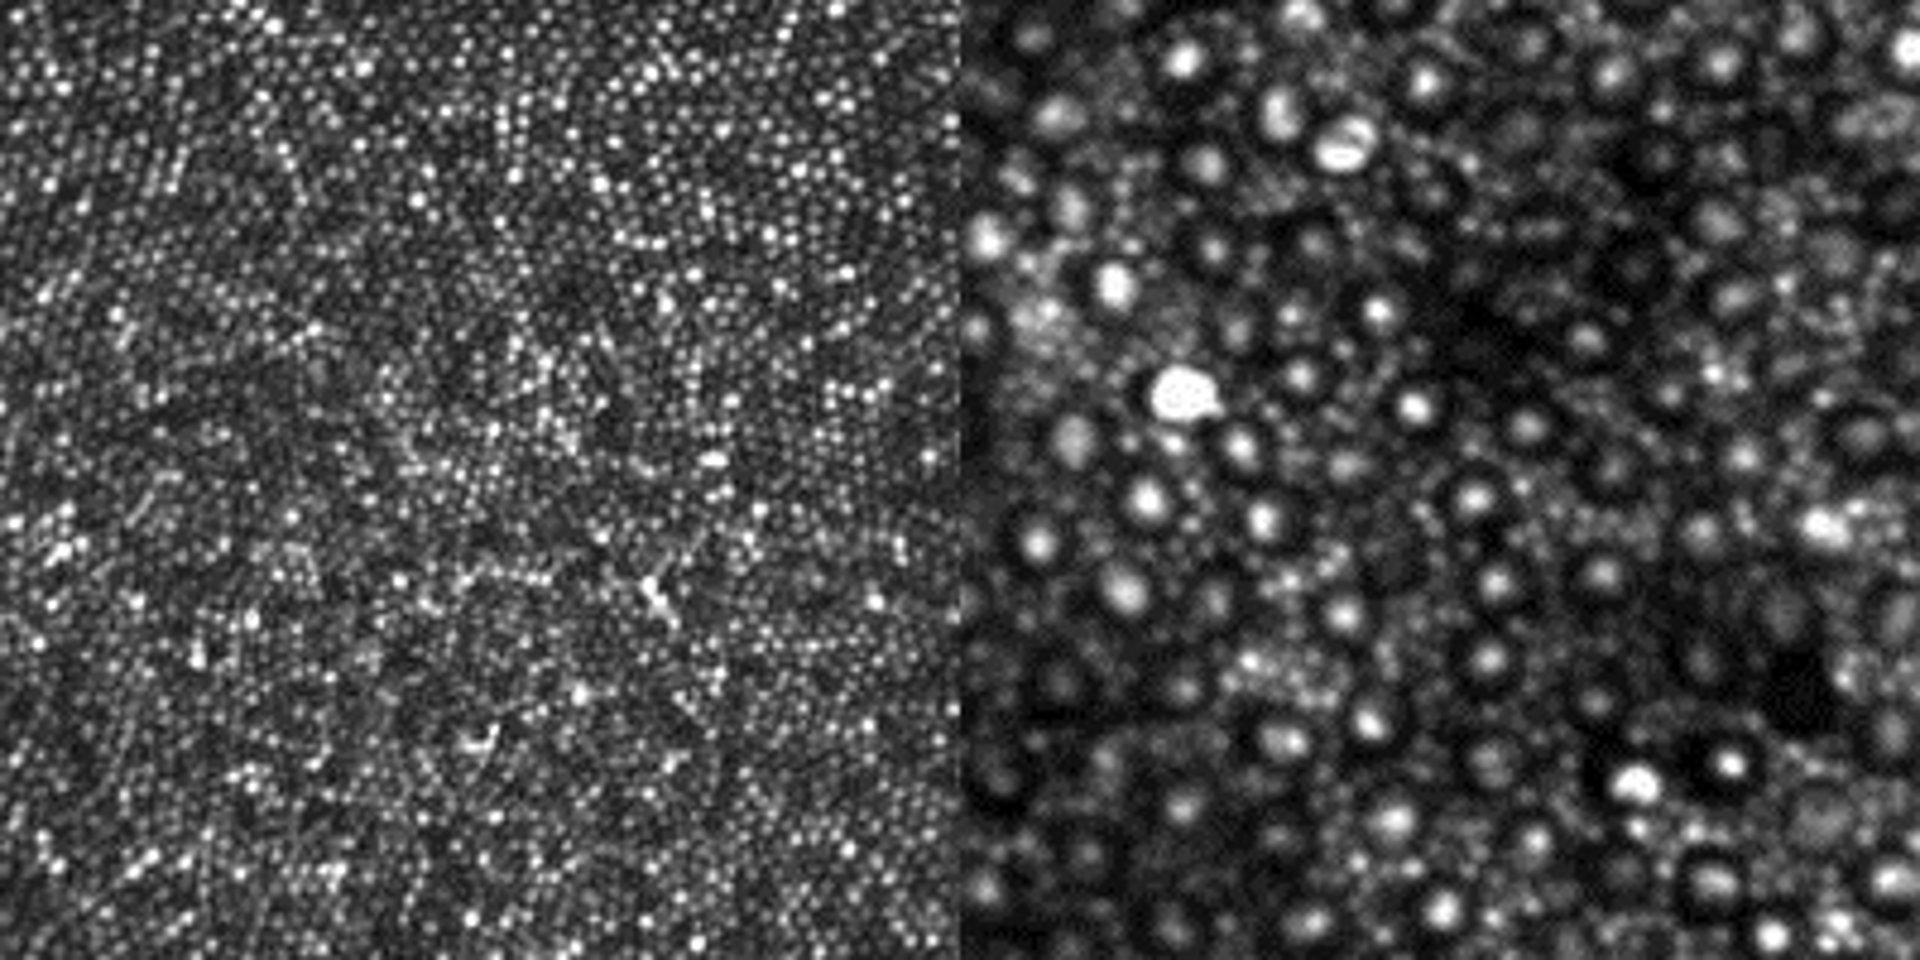

Científicos han logrado el hito de obtener imágenes claras y directas en un ojo vivo de los bastones, las pequeñas células sensibles a la luz.

Utilizando la óptica adaptativa, la misma tecnología que utilizan los astrónomos para estudiar las estrellas y galaxias distantes, se ha podido ver a través de la turbia distorsión de la parte externa del ojo, revelando su estructura celular con un detalle sin precedentes.

El avance, que marca el comienzo de una nueva era en la investigación de las enfermedades oculares, el diagnóstico y tratamiento es una mejora del diseño de un sistema no invasivo de imagen óptica adaptativa. Dubra y sus colegas fueron capaces de impulsar la resolución del dispositivo a límites ópticos de cerca de 2 micrones (un micrón es uan milésima de milímetro), o el diámetro aproximado de una solo bastón en el ojo humano.

Los bastones son mucho más numerosos que los conos y son mucho más sensibles a la luz. Con el método de diseño óptico demostrado por el equipo de Dubra, incluso los más pequeños conos en el centro de la retina, conocido como el centro de la fóvea, se pueden ver muy claramente. Los bastones se pueden ver claramente en un lugar menos central de la retina.